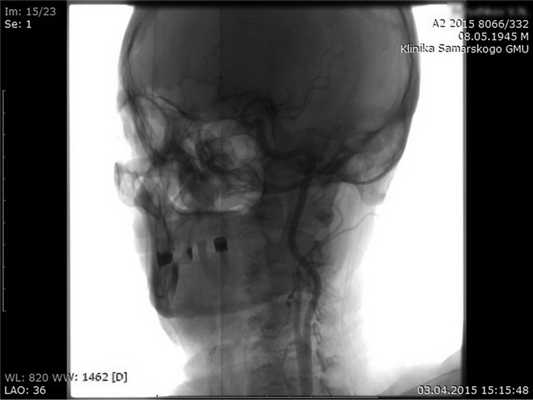

Установили коронарные стенты диаметром 3 мм, покрытые северолимусом. На момент окончания операции все сосуды проходимы (рис. 5).

Рис. 5. Послеоперационная ангиография пациента С.